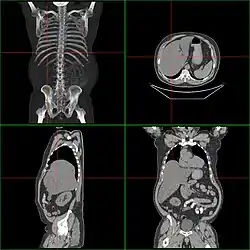

![]() Powiększona wątroba widoczna na TK | |

Hepatomegalia – termin medyczny oznaczający powiększenie wątroby.